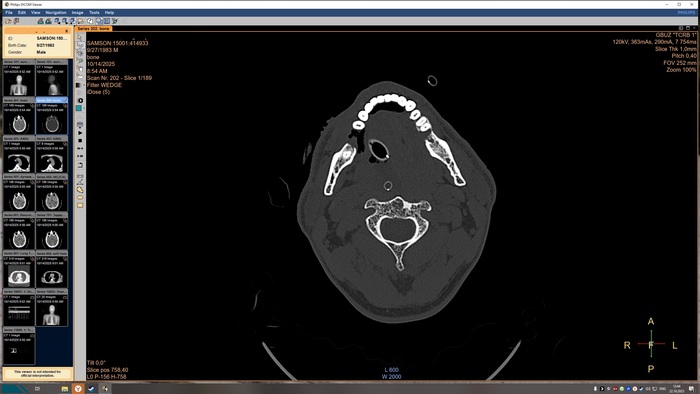

Описание КТ прикрепляю, а снимки будут в конце поста, по-другому у меня не получилось.

На топограмме, серии аксиальных срезов и реконструкций получены изображения суб- и

супратенториальных структур головного мозга от большого затылочного отверстия до крыши

черепа в нативном виде и в/в контрастированием. Определяются: справа четко

идентифицируемые внутричерепные интрапаренхиматозные гиперденсные неоднородные

очаги, копящее контрастное вещество, плотностью до 51-55ед.Х., размером: в проекции

лучистого венца 8х8х9 мм, в проекции продолговатого мозга 21х26х19 мм, Срединные

структуры мозга не смещены. Боковые желудочки: правый до 10,2 мм, левый до 12,9 мм,

третий-2,6 мм, четвёртый-13,8 мм. Селлярная и хиазмальная области без видимых

патологических изменений. Цистерны основания мозга, конвекситальные ликворные

пространства и борозды полушарий большого мозга сужены. Оболочки мозга без

особенностей. Миндалины мозжечка расположены соответственно возрасту. Дополнительных

образований и жидкостных скоплений в воздухоносных полостях височных костей с обеих

сторон, полости носа и его придаточных пазух не выявлено. Содержимое глазниц

визуализируется без особенностей. Признаков остеолитического, -пластического процессов,

аномалий развития и/или травматических повреждений костей черепа исследованного уровня

не выявлено. На прямой топограмме, серии аксиальных срезов и реконструкций получены

Заключение

КТ-признаки очаговых образований головного мозга. КТ-признаки правосторонней

верхнедолевой сегментарной б/пневмонии. ДИ ГОП.

Снимки КТ